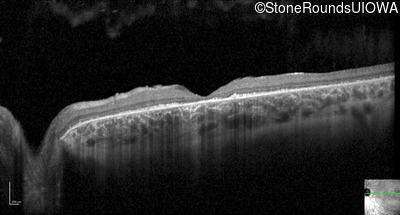

Optical Coherence Tomography - Right - 20/200 +2

Exemplar / OCT Stack

OCT Stack

Optical Coherence Tomography - Left - 20/200 +2